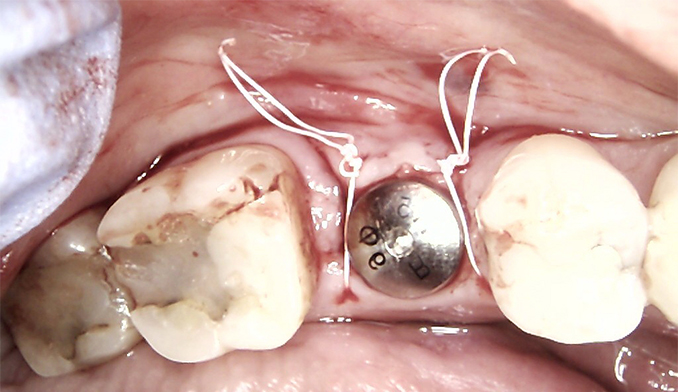

Immediate Implant Placement After Front Tooth Loss

The patient presented with a broken front tooth that could not be saved. We removed the tooth and immediately placed a dental implant to preserve the natural appearance. After four months of healing, a custom implant crown was placed, fully restoring the patient’s smile and function.